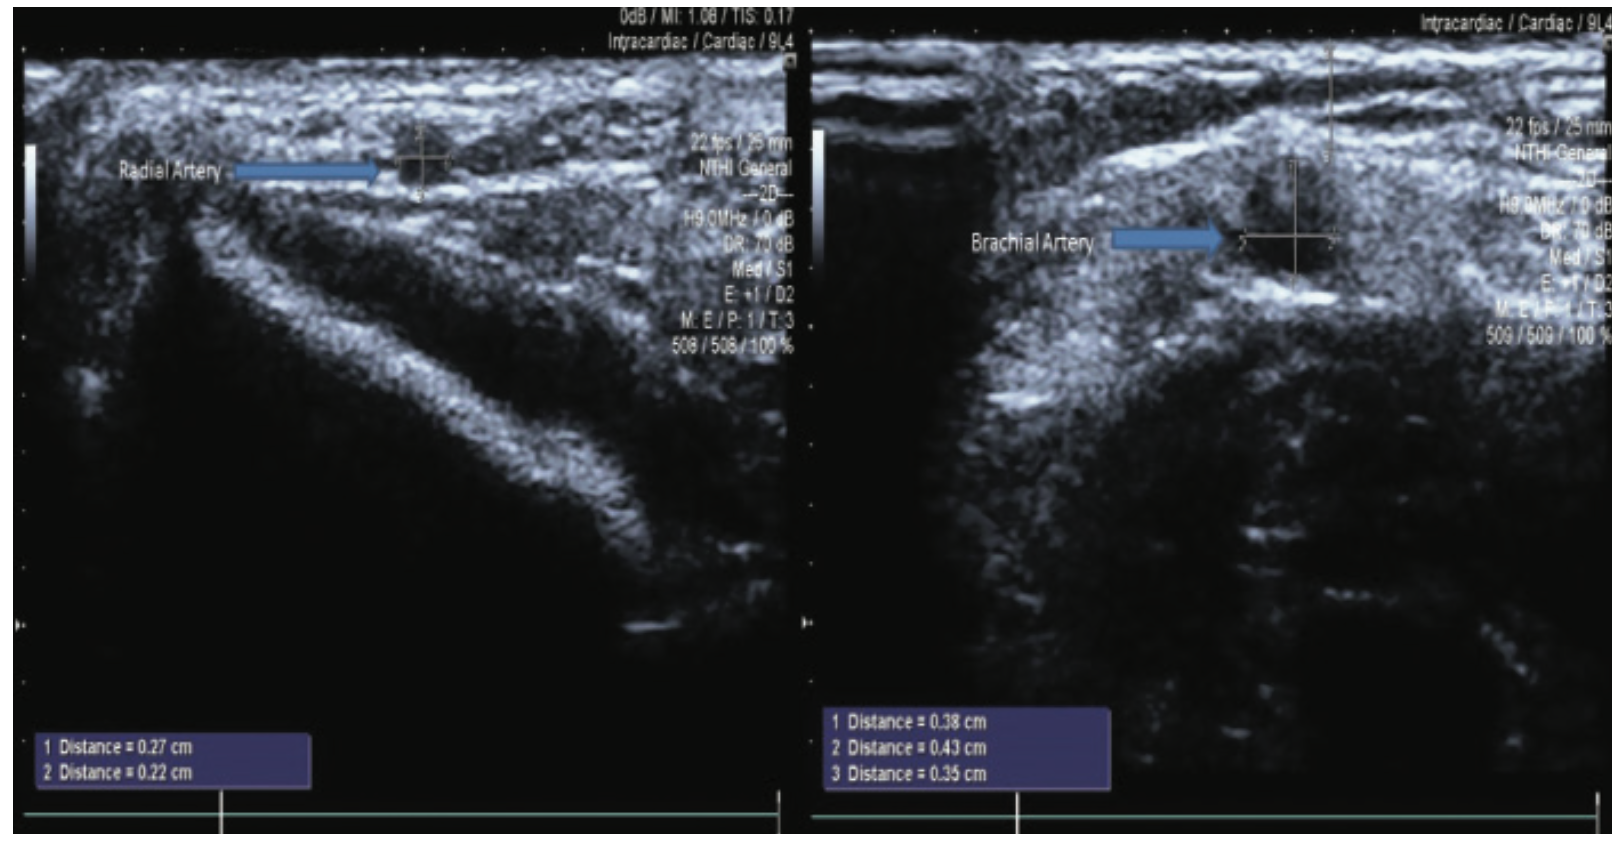

Radial Artery Access

As radial artery access becomes more common in coronary angiography, US guidance has benefits that may result in higher cannulation success rates, fewer total attempts, and decreased procedural time. US guidance is an easily learned technique to isolate the artery and determine size and depth4, and may decrease the time that it takes for successful radial artery access. In addition, successful US-guided insertion identifies vessel size to ensure that a 6 French sheath can be inserted (Figure 5). US guidance and first-time successful punctures also reduce the likelihood of spasm and thrombosis, and increase patient comfort.5 Therefore, US guidance should be considered for routine as well as potentially challenging radial artery access.